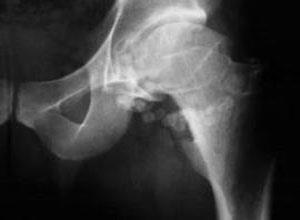

骨血管外皮细胞瘤

简介骨血管外皮细胞瘤是起源于骨血管Zimmerman外皮细胞的肿瘤,1942年首先由Stout描述。此瘤极为罕见,到目前国内外文献报道不足40例,1993年被WHO分为中间型血管外皮细胞瘤和恶性血管外皮细胞瘤两类。